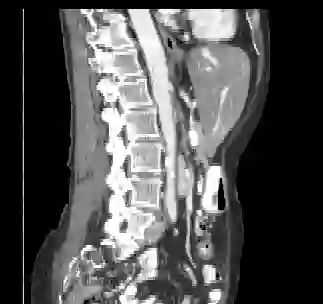

Recently, deep learning methods have achieved state-of-the-art performance in many medical image segmentation tasks. Many of these are based on convolutional neural networks (CNNs). For such methods, the encoder is the key part for global and local information extraction from input images; the extracted features are then passed to the decoder for predicting the segmentations. In contrast, several recent works show a superior performance with the use of transformers, which can better model long-range spatial dependencies and capture low-level details. However, transformer as sole encoder underperforms for some tasks where it cannot efficiently replace the convolution based encoder. In this paper, we propose a model with double encoders for 3D biomedical image segmentation. Our model is a U-shaped CNN augmented with an independent transformer encoder. We fuse the information from the convolutional encoder and the transformer, and pass it to the decoder to obtain the results. We evaluate our methods on three public datasets from three different challenges: BTCV, MoDA and Decathlon. Compared to the state-of-the-art models with and without transformers on each task, our proposed method obtains higher Dice scores across the board.